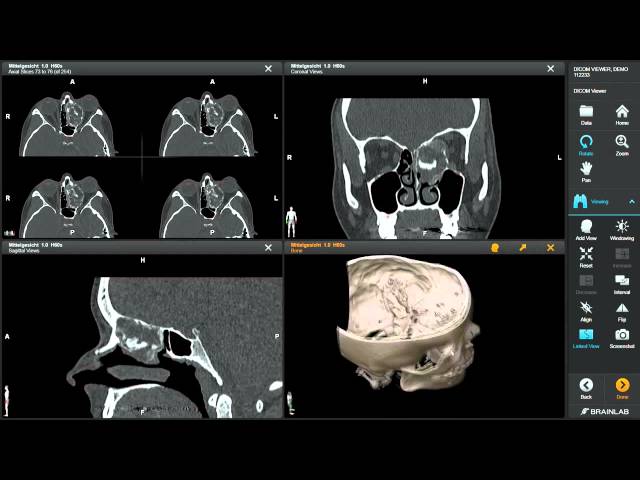

Apprehending DICOM Viewer Functions

DICOM viewers have more than simple image display functions. They understand embedded metadata and visual data. This is because window leveling assists in contrast optimization to diagnose properly. There is the zoom and pan functionality.

Multi-series and multi-frame navigation facilitates complicated research. Anatomical measurements are evaluated with the help of measurement tools. Clinical reporting is facilitated by the use of annotation features. There is the support of modality; it consists of CT, MRI, ultrasound, and X-ray.

Diagnostic errors are prevented by accurate rendering. There needs to be consistent performance on a variety of datasets. The knowledge of such functions aids the organizations in making the right decision on the viewing solutions.

Diagnostic reliability has a direct relationship with performance. The viewers are required to manipulate massive DICOM files in real-time. The accuracy rendering method maintains pixel accuracy and spatial resolution.

By providing high-bit-depth, the grayscale representation is correct. Image editing is enhanced by the use of a GPU. Form Hairs Consistency cross-platform compatible interfaces. Stability aids against crashing during important reviewing.

There is efficient caching, which enhances load times. Image reconstruction should not be unfaithful to the initial scans. Clinical interpretation is made possible through accurate visualization. The performance-oriented viewers increase trust and diagnostic consistency.